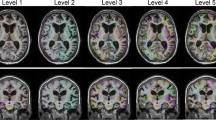

Diffusion tensor imaging (DTI) fractional anisotropy (FA) maps are increasingly incorporated into clinical practice [10, 11] due to their rapid acquisition and availability on commercial DTI software packages. The unique anatomical information afforded by its color encoding for directional molecular water diffusion allows for consistent identification of major fiber tracts. In NPH, gross deformation of the red-encoded callosal commissural fibers is well depicted on color FA maps (Fig. 1). We propose the splenial angle (SA) as a novel alternative axial angular index of lateral ventricular dilatation for the clinical workup of NPH. We hypothesize that the SA could quantitate lateral ventricular distension in NPH as the CA does. We evaluated its (i) values, reproducibility, and ease of training; (ii) temporal changes in NPH patients after shunt surgery; and (iii) performance in differentiating NPH from Alzheimer’s disease (AD), Parkinson’s disease (PD), and healthy control (HC), compared to EI and CA.

Consecutive axial diffusion tensor imaging (DTI) fractional anisotropy (FA) maps in a healthy control subject and a patient with idiopathic normal pressure hydrocephalus (NPH) demonstrating gross deformation of the red-encoded callosal commissural fibers, and depiction of the splenial angle (SA) as a simple angular index (inset) of the compression and stretching of the posterior callosal commissural fibers alongside the posterior-medial walls of the lateral ventricles. The SA is placed over the limbs of the forceps major and pivoted over the midline on the first axial slice containing the complete body of the corpus callosum. Note the severely narrowed SA in the NPH patient arising from the gross ventricular distension compared to that in the HC

Image analysis was performed on the brain MRIs of 76 subjects comprising 19 NPH patients, and equal numbers each of AD, PD, and HC subjects. EI, CA, and SA measurements (Fig. 2) were made by 2 blinded independent raters: a neuroradiologist with more than 20 years of experience and a radiology research assistant. The EI [3,4,5] (Fig. 2a) was measured as the maximal width of the frontal horns of the lateral ventricles to the maximal internal diameter of the cranium on the same axial FLAIR image. The CA [7, 8] (Fig. 2b) was measured as the angle subtended by the roof of both lateral ventricles on a coronal MPRAGE image through the PC. Care was undertaken, during multiplanar reformatting on the 3D high-resolution MPRAGE series, to ensure that the coronal image upon which the CA was measured was truly orthogonal to the AC-PC plane as determined on multiplanar views.

Evans’ index (EI), callosal angle (CA), and splenial angle (SA)measured on brain MRI in healthy controls (HC), Parkinson’s disease (PD), Alzheimer’s disease (AD), and normal pressure hydrocephalus (NPH) patients. a Axial FLAIR images demonstrating EI as a ratio of the maximal width of the frontal horns of the lateral ventricles (short blue line) against the maximal internal diameter of the cranium (long blue line) on the same section. b Left sagittal images depicting the coronal plane (red line) orthogonal to the anterior-posterior commissural (AC-PC) plane (blue line), and right coronal images demonstrating the CA subtended against the roof of the lateral ventricles. c Axial diffusion tensor imaging (DTI) color FA images containing the complete red-encoded callosal body depicting the SA subtended over the limbs of the forceps major and pivoted over the midline. Note the severely narrowed SA in an NPH patient arising from deformation of the red-encoded posterior callosal commissural fibers secondary to gross ventricular distension

Using the DTI color FA maps, the SA was measured on the first axial slice containing the complete body of the corpus callosum encoded in red, when scrolling in a caudocranial direction (Figs. 1 and 2c). The SA is an angular quantitative measure of the compression and stretching of the red-encoded posterior callosal commissural fibers alongside the posterior-medial walls of the lateral ventricles. The angle is pivoted over the midline with its arms aligned along the center of limbs of the forceps major. The forceps major is more severely compressed by the ventricular distension than the forceps minor in NPH patients (Fig. 1), and as a result, the angular pivot of the SA thus measured lies farther anteriorly in NPH patients than AD, PD, and HC subjects (Fig. 2c). In subjects where the thicker callosal body is completely imaged on 2 slices, the caudal image is used for the SA measurement.

Both the EI and SA measurements were easy to train in. The research assistant readily acquired proficiency in effecting reproducible EI and SA measurements after a morning of training. In contrast, training to effect reproducible CA measurements extended over a month. Figures 1 and 2 demonstrate representative SA measurements for HC, PD, AD, and NPH groups. The red-encoded posterior commissural fibers at the body of the corpus callosum and forceps major were more severely deformed by the gross ventricular distension than the forceps minor and anterior callosal fibers in NPH patients. The SA (Figs. 1 and 2c) is well placed to document these morphological changes, and severely narrowed in NPH patients, in stark contrast to non-NPH subjects. Figure 3 shows the multiple potential pitfalls to positioning a “true” coronal plane and its impact on CA variability. Much effort was expended learning to reformat and position a “true” coronal MPRAGE image at the PC. Specifically, learning anatomical landmarks on the high-resolution 3D MPRAGE sequence (using the internal auditory canal and inner ear structures) to place the coronal image without right-left rotations protracted training. There was greater variability in the CA with erroneous acute/obtuse angulation (Fig. 3a) than with lateral right-left rotations of the coronal plane (Fig. 3b).